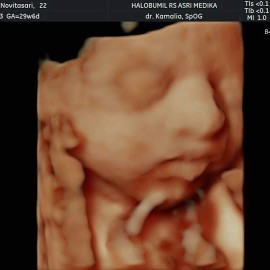

ini kmren 27wk & 34wk